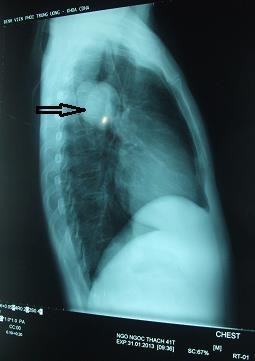

Cụ thể, TS Đề cho biết, bệnh nhân đầu tiên là T. 42 tuổi (Thanh Hóa) nhập viện vào tháng 3/2013.

Hình ảnh bệnh nhân ở Thanh Hóa bị sán chó làm tổ tạo u trong phổi. |

“Bệnh nhân được chẩn đoán u phổi và bị chỉ định cắt bỏ 1 thùy phổi kèm khối u. Khối u của bệnh nhân là một bọc nước. Tuy nhiên, chúng tôi vô cùng kinh hãi khi trong bọc nước là hàng nghìn đầu sán đang ngoe nguẩy. Kết quả xét nghiệm khẳng định là loại sán dây chó”, TS Đề nói.